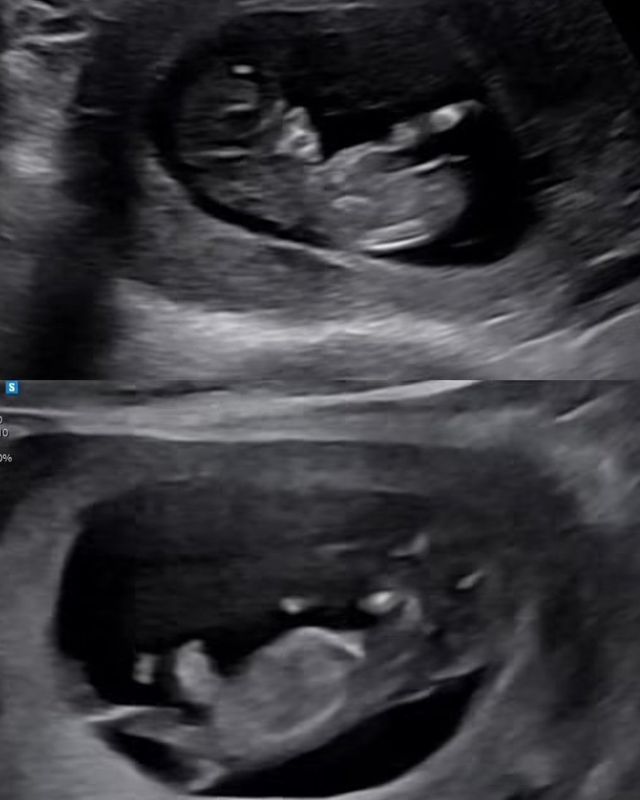

코미디언 임라라가 남편 손민수와 D라인을 뽐냈다.

임라라는 28일 자신의 소셜미디어에 “입덧하는 동안 사진을 너무 못 올려서 20주 넘어서 올리는 14주차 사진”이라는 글과 함께 여러 장의 사진을 게재했다. 사진 속 임라라는 통통하게 나온 D라인을 자랑하며 환한 미소를 짓고 있다. 남편 손민수도 배를 내밀고 장난스럽게 포즈를 취해 유쾌한 분위기를 자아냈다.

임라라는 “쌍둥이라서 배가 쑥쑥 나오고 있어요. 제가 남긴 음식 다 먹던 민수는 만삭이래요”라며 손민수를 향한 애정을 드러냈다. 또 “입덧하는 동안 너무 외로웠다”며 “이제 조금씩 자주 인스타로 소통하겠다”고 밝혔다.